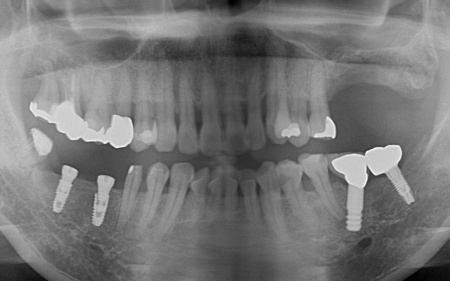

骨吸収の影響で温存が難しい左上奥歯(第1大臼歯、第2大臼歯)と、大きく傾いてしまっている右下の親知らず(第3大臼歯)の3本は抜く必要があることをお伝えしました。

左上については、顎の骨が大きく失われているため、骨を再生させる処置「GBR(骨再生誘導法)」を実施してインプラントを支えるために必要な骨量を確保したうえで、インプラントを埋入する計画を立てました。

経過観察後、十分な骨量を確保できたことを確認し、インプラントを埋入しました。

次に、右下に装着されているブリッジを除去してから右下の親知らずを抜き、欠損部(第1大臼歯、第2大臼歯の部分)にインプラントを埋入しました。

最後に、完成した人工歯をインプラントに取り付け、噛み合わせや見た目に問題がないことを確認し、治療を終了しました。